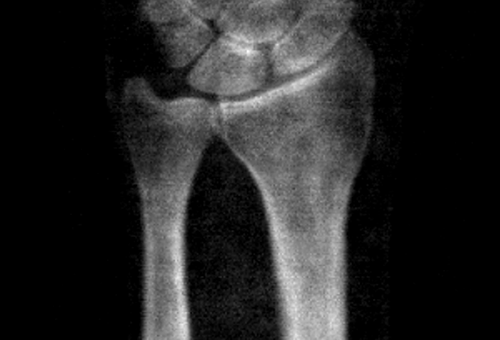

HR-pQCT Radius & Tibia Seg

HR-pQCT Radius & Tibia Seg Radius/Tibia Seg Repo

Machine learning for segmenting the distal radius and distal tibia from HR-pQCT scans as an alternative to the morphological processing approach.